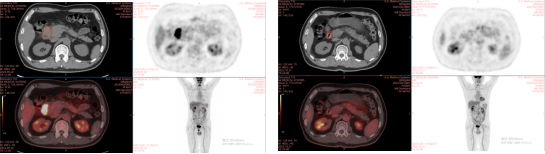

1. Brief Medical History:

The patient, Ding Jian, male, 65 years old, chief complaint: discovered malignant tumor of the duodenum 3 weeks ago. On August 28, 2024, an abdominal + pelvic CT scan at Xi’an Ninth Hospital indicated a suspected occupying lesion in the descending part of the duodenum (approximately 5.3 × 4.1 × 4.6 cm in size), with scattered enlarged lymph nodes around the lesion and in the retroperitoneum (approximately 1.8 × 1.9 cm in size). Pathological results suggested a malignant tumor of the duodenum. On September 18, 2024, a puncture biopsy under endoscopic ultrasound guidance at our hospital showed: (descending part of the duodenum) malignant tumor. Based on morphological changes and immunohistochemistry results, it was highly suspected to be ALK-positive anaplastic large cell lymphoma. The definitive diagnosis was: Malignant tumor of the duodenum, ALK-positive anaplastic large cell lymphoma, IPI score 1, Lugano stage IIE, Ann Arbor stage IIE, TNM staging of gastrointestinal lymphoma (Paris staging) IIE; KPS score: 90.

Carbon ion therapy was initiated on September 30, 2024: PTV: 40Gy (RBE)/10Fx. On September 23, 2024, one cycle of systemic intravenous chemotherapy with the XELOX regimen was administered, specifically: Oxaliplatin (130mg/m²) 244mg IV drip d1 + Capecitabine tablets (800mg/m²) 1.5g PO Bid d1-14 Q3W. On October 17, 2024, one cycle of systemic intravenous chemotherapy with the CHP regimen + targeted therapy with Brentuximab Vedotin was administered, specifically: Cyclophosphamide (750mg/m²) 1300mg IV drip d1 + Doxorubicin (40mg/m²) 70mg IV drip d1 + Prednisone 100mg PO d1-5 Q3W + Brentuximab Vedotin (1.8mg/kg) 100mg IV drip d1 Q3W.

2. Imaging Comparison: